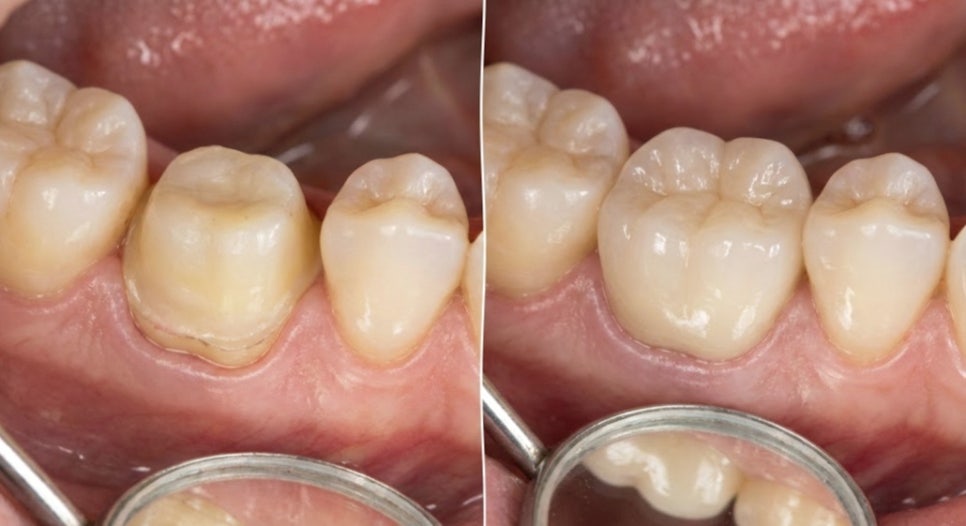

- 튼튼함과 심미성을 동시에,

지르코니아크라운

과거에는 보통 크라운이라고 하면

금니를 먼저 떠올리시기도 하지만,

최근에는 자연치와 유사한 색상의

지르코니아를 선호하는데요.

이 재료는 인공 다이아몬드라 불릴 만큼

강도가 매우 뛰어난 것이 특징입니다.

부식의 우려가 적고 생체 친화적이라

잇몸 경계 부분이 검게 변하는 현상을

개선하는 데 도움을 줄 수 있습니다.

특히 치아의 손상 범위가 넓거나

신경 치료를 병행해야 되는 경우,

치아 전체를 감싸 보호해 주는

지르코니아크라운 방식이 적합할 수 있습니다.